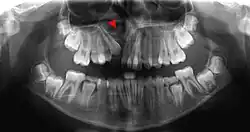

X-ray showing alveolar defect causing cleft lip and cleft palate

Alveolar bone grafting in the mixed dentition is an essential part of the reconstructive journey for cleft lip and cleft palate patients. The reconstruction of the alveolar cleft can provide both aesthetic and practical advantages to the patient.[25] Alveolar bone grafting can also bring about the following benefits: stabilisation of the maxillary arch; aid of eruption of the canine and sometimes lateral incisor eruption; offering bony support to the teeth lying next to the cleft; elevate the alar base of the nose; aid sealing of oro-nasal fistula; permit insertion of a titanium fixture in the grafted region and achieve good periodontal conditions within and next to the cleft.[26] The timing of the alveolar bone grafting takes into consideration both eruption of the canine and lateral incisor. The optimal time for bone grafting surgery is when a thin shell of bone still covers the soon erupting lateral incisor or canine tooth close to the cleft.[26]